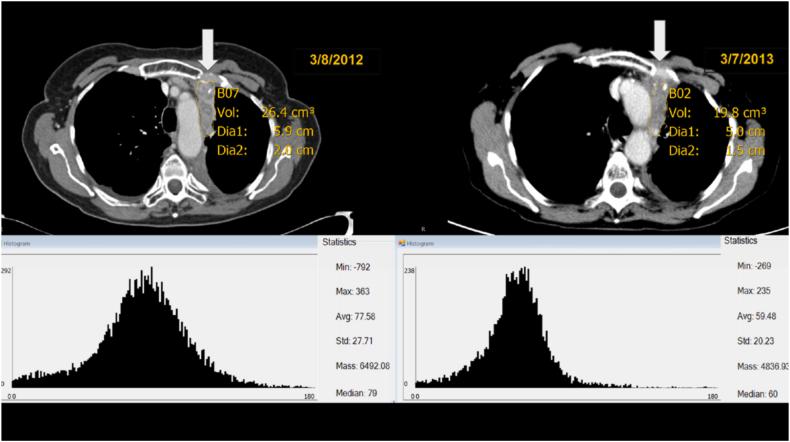

Adenoid cystic carcinoma (ACC) is a rare salivary gland cancer. The vast majority of clinical trials evaluating systemic therapy efficacy in solid tumors use the Response Evaluation Criteria in Solid Tumors (RECIST) to measure response that is limited to 2 dimensional only evaluations, not taking volume or density into account. The indolent behavior ACC represents a challenge toward an appropriate evaluation of therapy response. Objectives: 1) To describe and contrast volumetric and density changes at each time-point, including changes noted from baseline to best response, to currently used 2 dimensional-only criteria (RECIST) and 2) To report the coefficient of variation in volume measurement among three reviewers on a subset of ACC patients.

We retrospectively assessed a cohort of 18 prospectively treated patients with ACC in a phase 2 trial with vorinostat using a volumetric (viable tumor volume, VTV) and density criteria. Three independent and blinded observers segmented target lesions across a sample of randomly selected computed tomography (CT) exams to examine inter-observer variation.

We found that the average coefficient of variation among observers for all target lesions was 16.1%, with lung lesions displaying a smaller variation at 14.0% (p-value >0.17). We describe examples of decrease in volume and density in several lesions despite stable disease by RECIST.

腺样囊性癌(ACC)是一种罕见的唾液腺癌。绝大多数评估实体瘤全身治疗疗效的临床试验使用实体瘤疗效评价标准(RECIST)来衡量反应,该标准仅限于二维评估,未考虑体积或密度。ACC的惰性行为对治疗反应的恰当评估构成挑战。目的:1)描述并对比每个时间点的体积和密度变化,包括从基线到最佳反应的变化,与目前仅使用的二维标准(RECIST)进行对比;2)报告在一部分ACC患者中,三位评估者对体积测量的变异系数。

我们回顾性评估了一项在2期试验中使用伏立诺他对18例前瞻性治疗的ACC患者的队列,采用体积(存活肿瘤体积,VTV)和密度标准。三位独立且不知情的观察者在随机选择的计算机断层扫描(CT)检查样本中对靶病变进行分割,以检查观察者间的差异。

我们发现,所有靶病变观察者间的平均变异系数为16.1%,肺部病变的变异较小,为14.0%(p值>0.17)。我们描述了几个病变尽管按RECIST标准疾病稳定,但体积和密度却减小的例子。